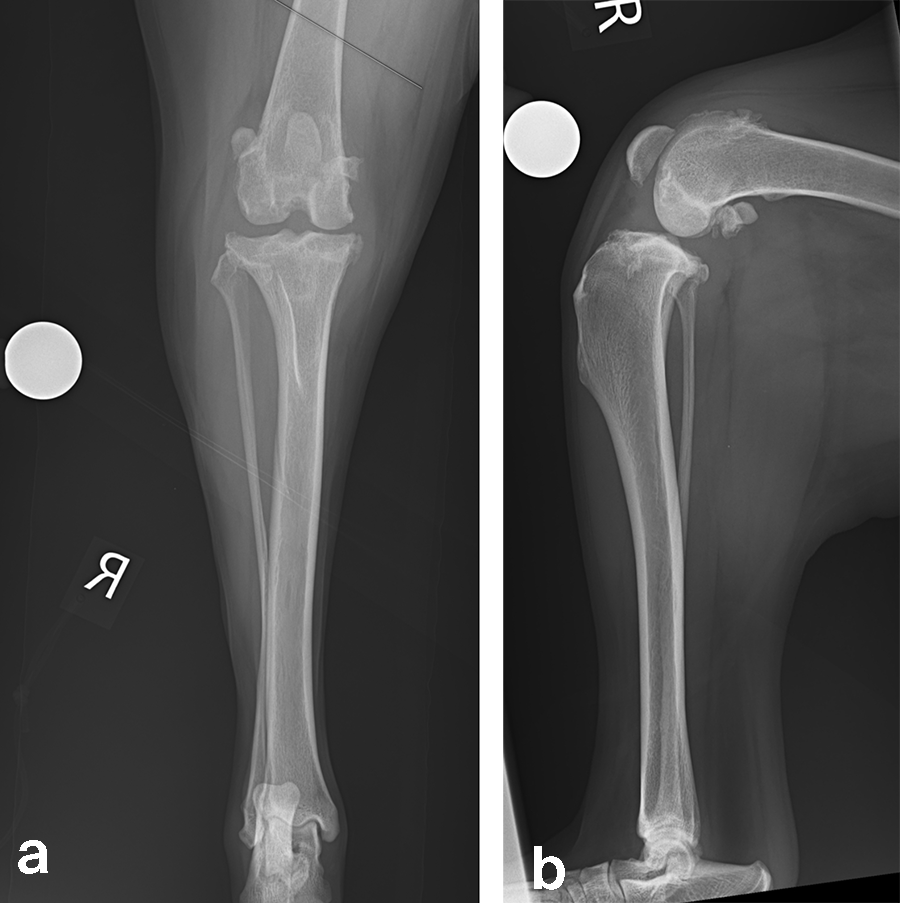

A 32 kg male neutered Golden Retriever presented with a recent deterioration of chronic right hind limb lameness. Physical examination revealed a cranial cruciate ligament rupture.

Case 2: Rosie, 3‐year‐old black Labrador Retriever, 23.3 kg

A 23.3 kg 3-year-old spayed female black Labrador Retriever presented with a history of chronic, progressive left pelvic limb lameness. Her clinical examination was suggestive of left cranial cruciate ligament (CCL) rupture. Medical and surgical treatment options were discussed with the clients. They elected to have Rosie’s knee treated with arthroscopy and TPLO.